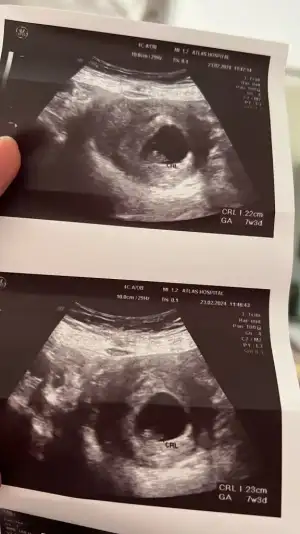

Nub teorisine göre cinsiyet tahmini yapabilen var mııı

Banada yorum yaparmisiniz acaba ilk foto 13+6 Ken olan ulturoson resmi ikincide 6+7 haftalık ulturoson resmi şuan ,16 haftaligiz fktotumuz hala cinsiyet söylemedi